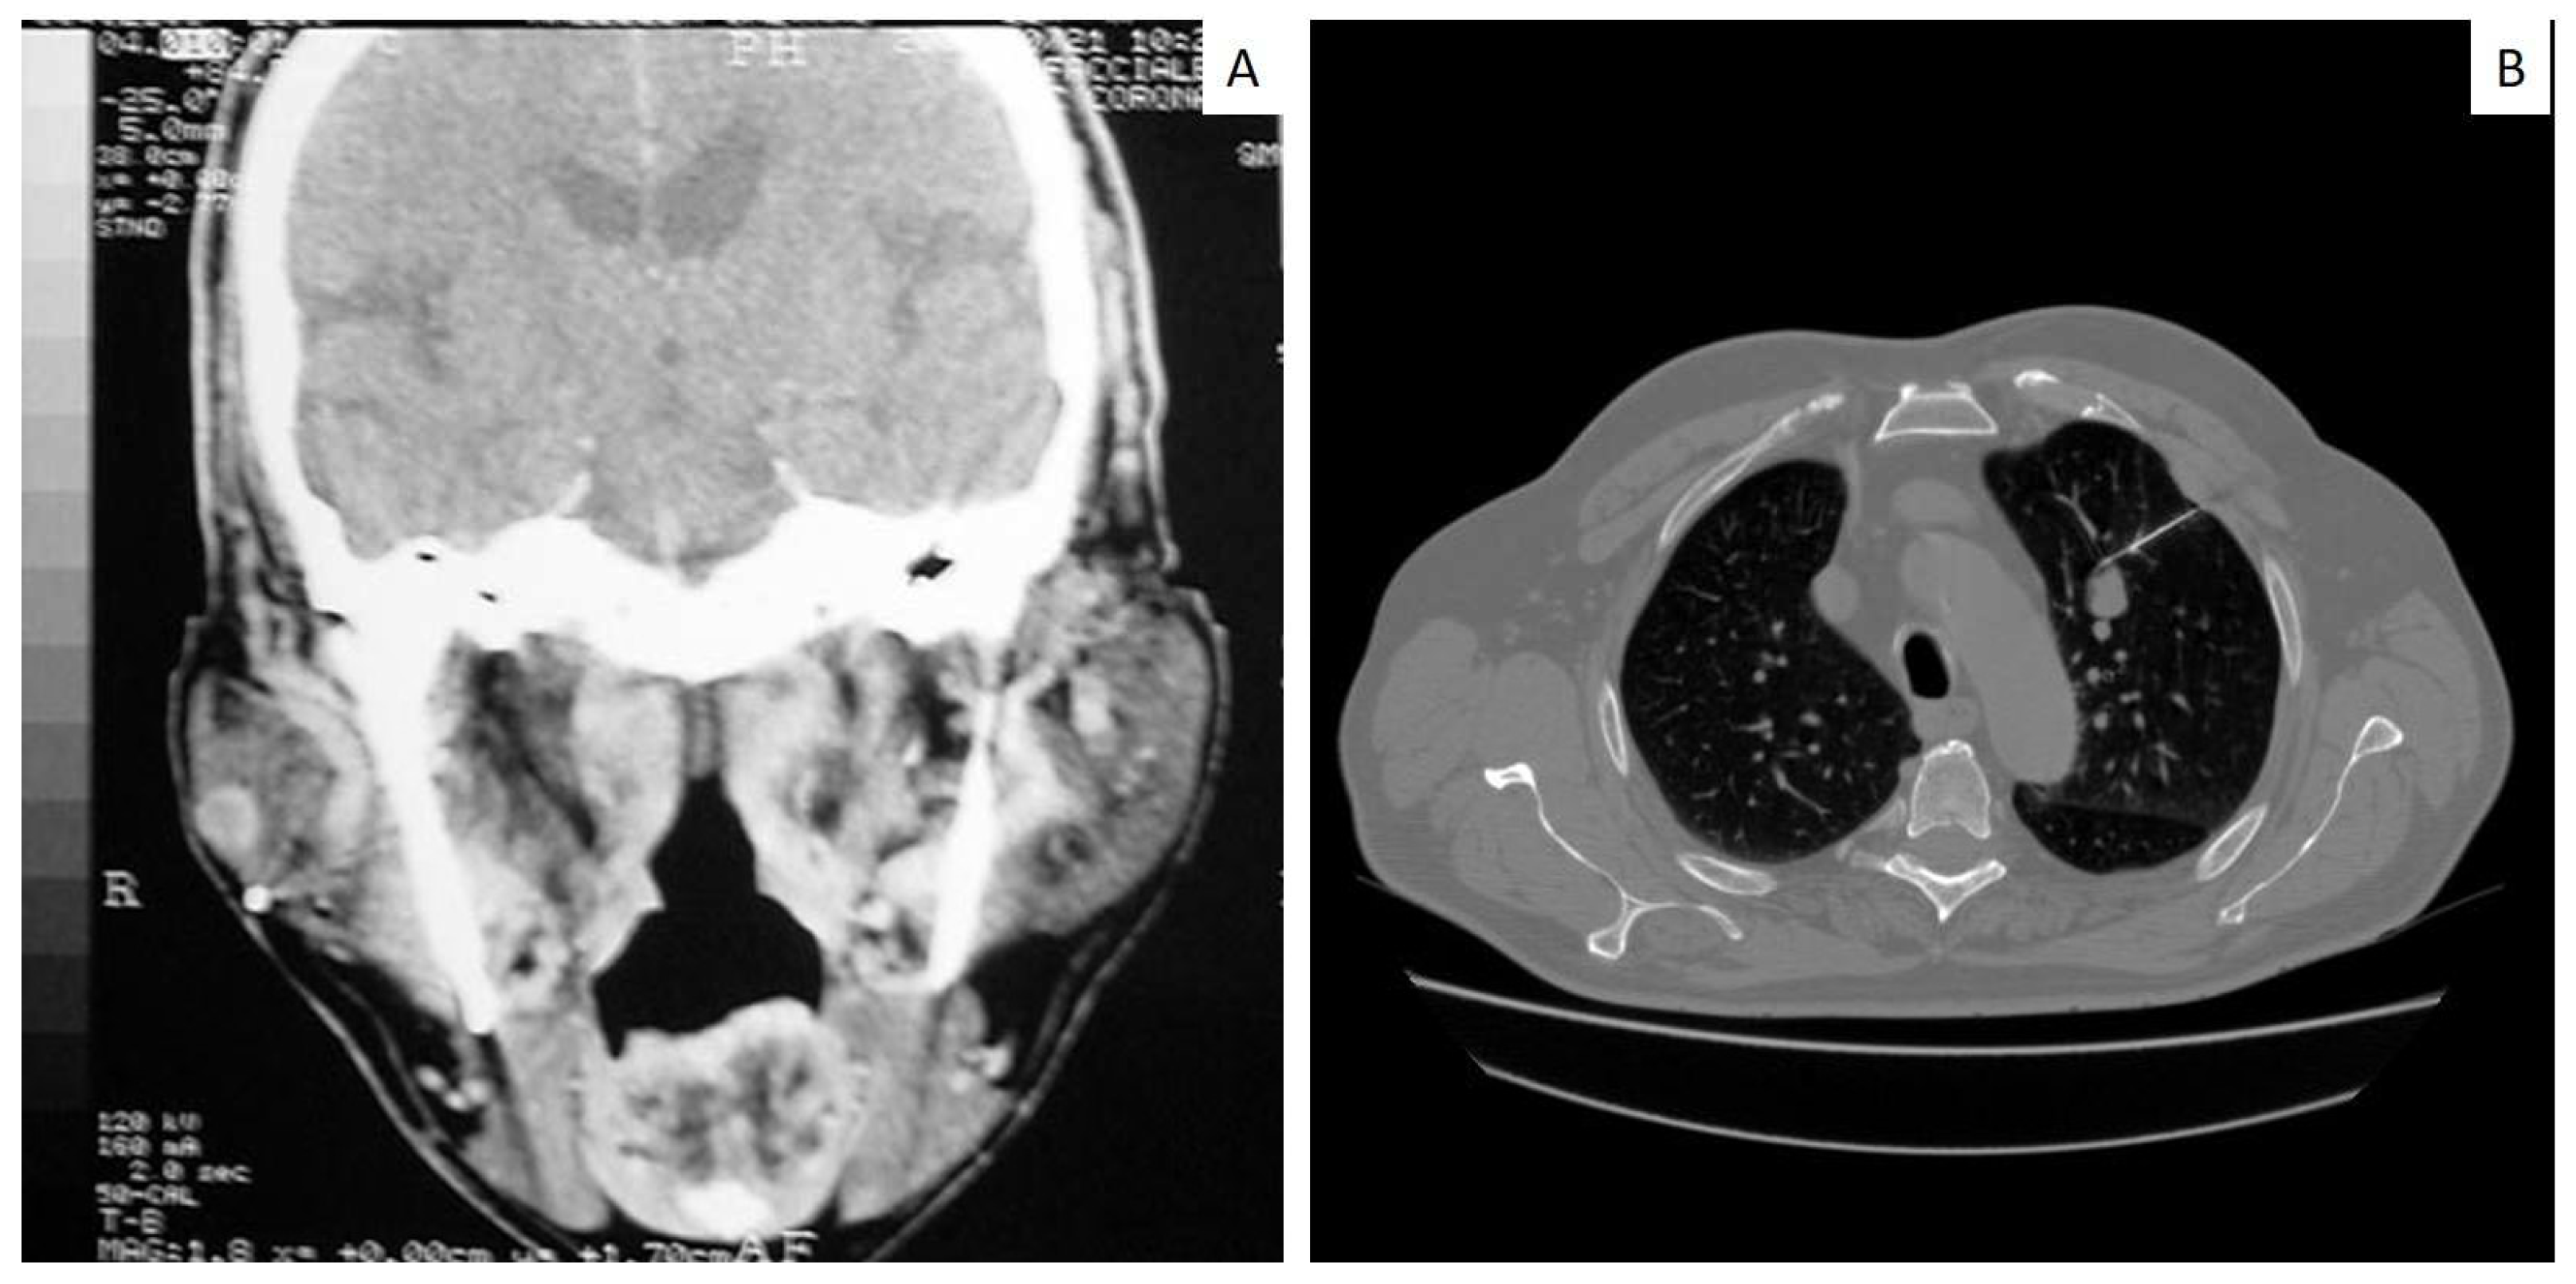

| Case | Age | Sex | Site/Sites | Primary Lung Tumor | Other Sites | First Sign of Disease |

|---|---|---|---|---|---|---|

| 1 | 43 | M | Submandibular lymph nodes | Non small cell carcinoma | n.a. | Yes |

| 2 | 52 | M | Submandibular lymph nodes | Non small cell carcinoma | n.a. | No |

| 3 | 65 | M | Gingiva | Non small cell carcinoma | n.a. | No |

| 4 | 82 | F | Gingiva | Squamous carcinoma | n.a. | No |

| 5 | 57 | M | Mandible | Non small cell carcinoma | n.a. | No |

| 6 | 68 | M | Submandibular lymph nodes | Non small cell carcinoma | n.a. | No |

| 7 | 62 | M | Gingiva | Non small cell carcinoma | n.a. | No |

| 8 | 67 | F | Submandibular lymph nodes | Non small cell carcinoma | n.a. | No |

| 9 | 50 | M | Submandibular lymph nodes | Squamous carcinoma | n.a. | Yes |

| 10 | 79 | M | Gingiva/palate | Non small cell carcinoma | n.a. | Yes |

| 11 | 65 | M | Gingiva/tongue | Squamous carcinoma | n.a. | No |

| 12 | 57 | M | Submandibular lymph nodes | Small cell carcinoma | n.a. | No |

| 13 | 65 | M | Submandibular lymph nodes | Squamous carcinoma | n.a. | No |

| 14 | 80 | M | Mandible | Squamous carcinoma | Vertebra | No |

| 15 | 67 | M | Maxillary gingiva | Squamous carcinoma | Vertebra | No |

| 16 | 65 | M | Parotid gland | Small cell carcinoma | n.a. | Yes |

| 17 | 70 | F | Maxillary gingiva Around dental implant | Small cell carcinoma | n.a. | Yes |

| 18 | 62 | M | Maxilla gingiva Around dental implant | Adenocarcinoma | n.a. | Yes |

| 19 | 65 | F | Tongue | Small cell carcinoma | n.a. | Yes |

| 20 | 72 | F | Maxillary gingiva | Adenocarcinoma | n.a. | Yes |

| 21 | 66 | M | Tongue | Small cell carcinoma | Brain | No |